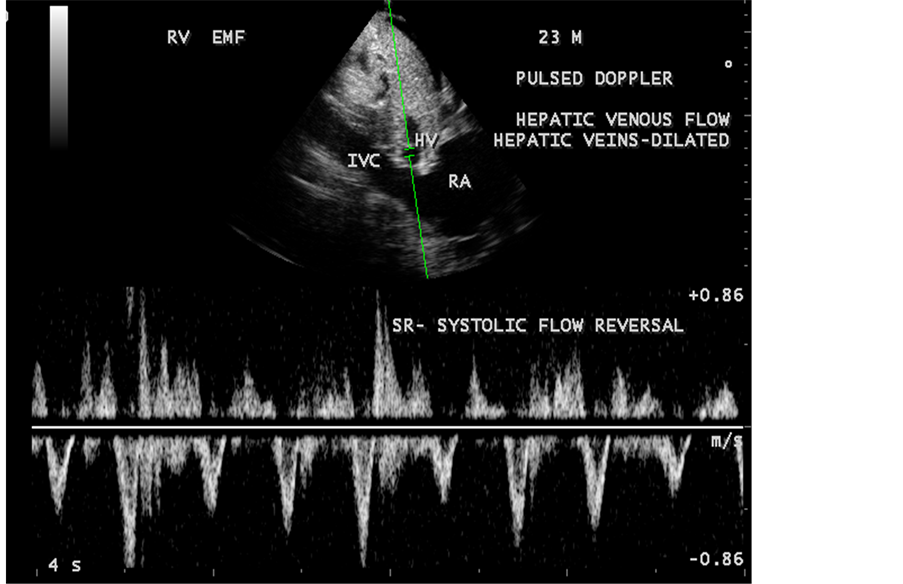

pressure 100/70 mmHg. Auscultation revealed diminished breath sounds on the right side of the chest with a dull note on percussion and a loud P2 (pulmonic component of second heart sound) with grade 2/6 soft systolic murmur over the lower left sternal border which increases in intensity with deep inspiration (Carvallo’s sign) suggesting tricuspid regurgitation. ECG revealed no arrhythmias and X-ray chest showed right- sided pleural effusion and extensive calcification over the cardiac shadow as shown in Figure 9. Transthoracic echocardiography revealed apical fibrosis of right ventricle, moderate pericardial effusion, right atrial dilatation as shown in Figure 10 and Figure 12, suggesting right ventricular endomyocardial fibrosis and severe tricuspid regurgitation as in Figure 11, Figure 13 and Figure 14 indicates coexisting pulmonary hypertension due to pulmonary damage caused by tuberculosis as shown in Figure 13 and free RV outflow tract as in Figure 15. Patient was treated with antituberculous drugs, antifailure measures such as digoxin and diuretics, ascites fluid tapping and antibiotics. He showed mild improvement in his symptoms.

Figure 14. Pulsed Doppler showing systolic flow reversal in hepatic venous flow due to severe tricuspid regurgitation and dilated hepatic veins.

Figure 15. RV outflow tract (RVOT) is free of fibrosis and fibrous strands stand as ridge in Endomyocardial fibrosis with tuberculosis.